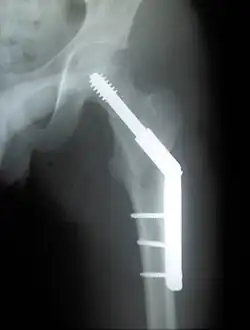

- El término "elevador de tensiones" se usa en ortopedia para referirse a un punto donde es posible que un implante provoque una concentración de tensiones que pueda llevar a un fallo mecánico.